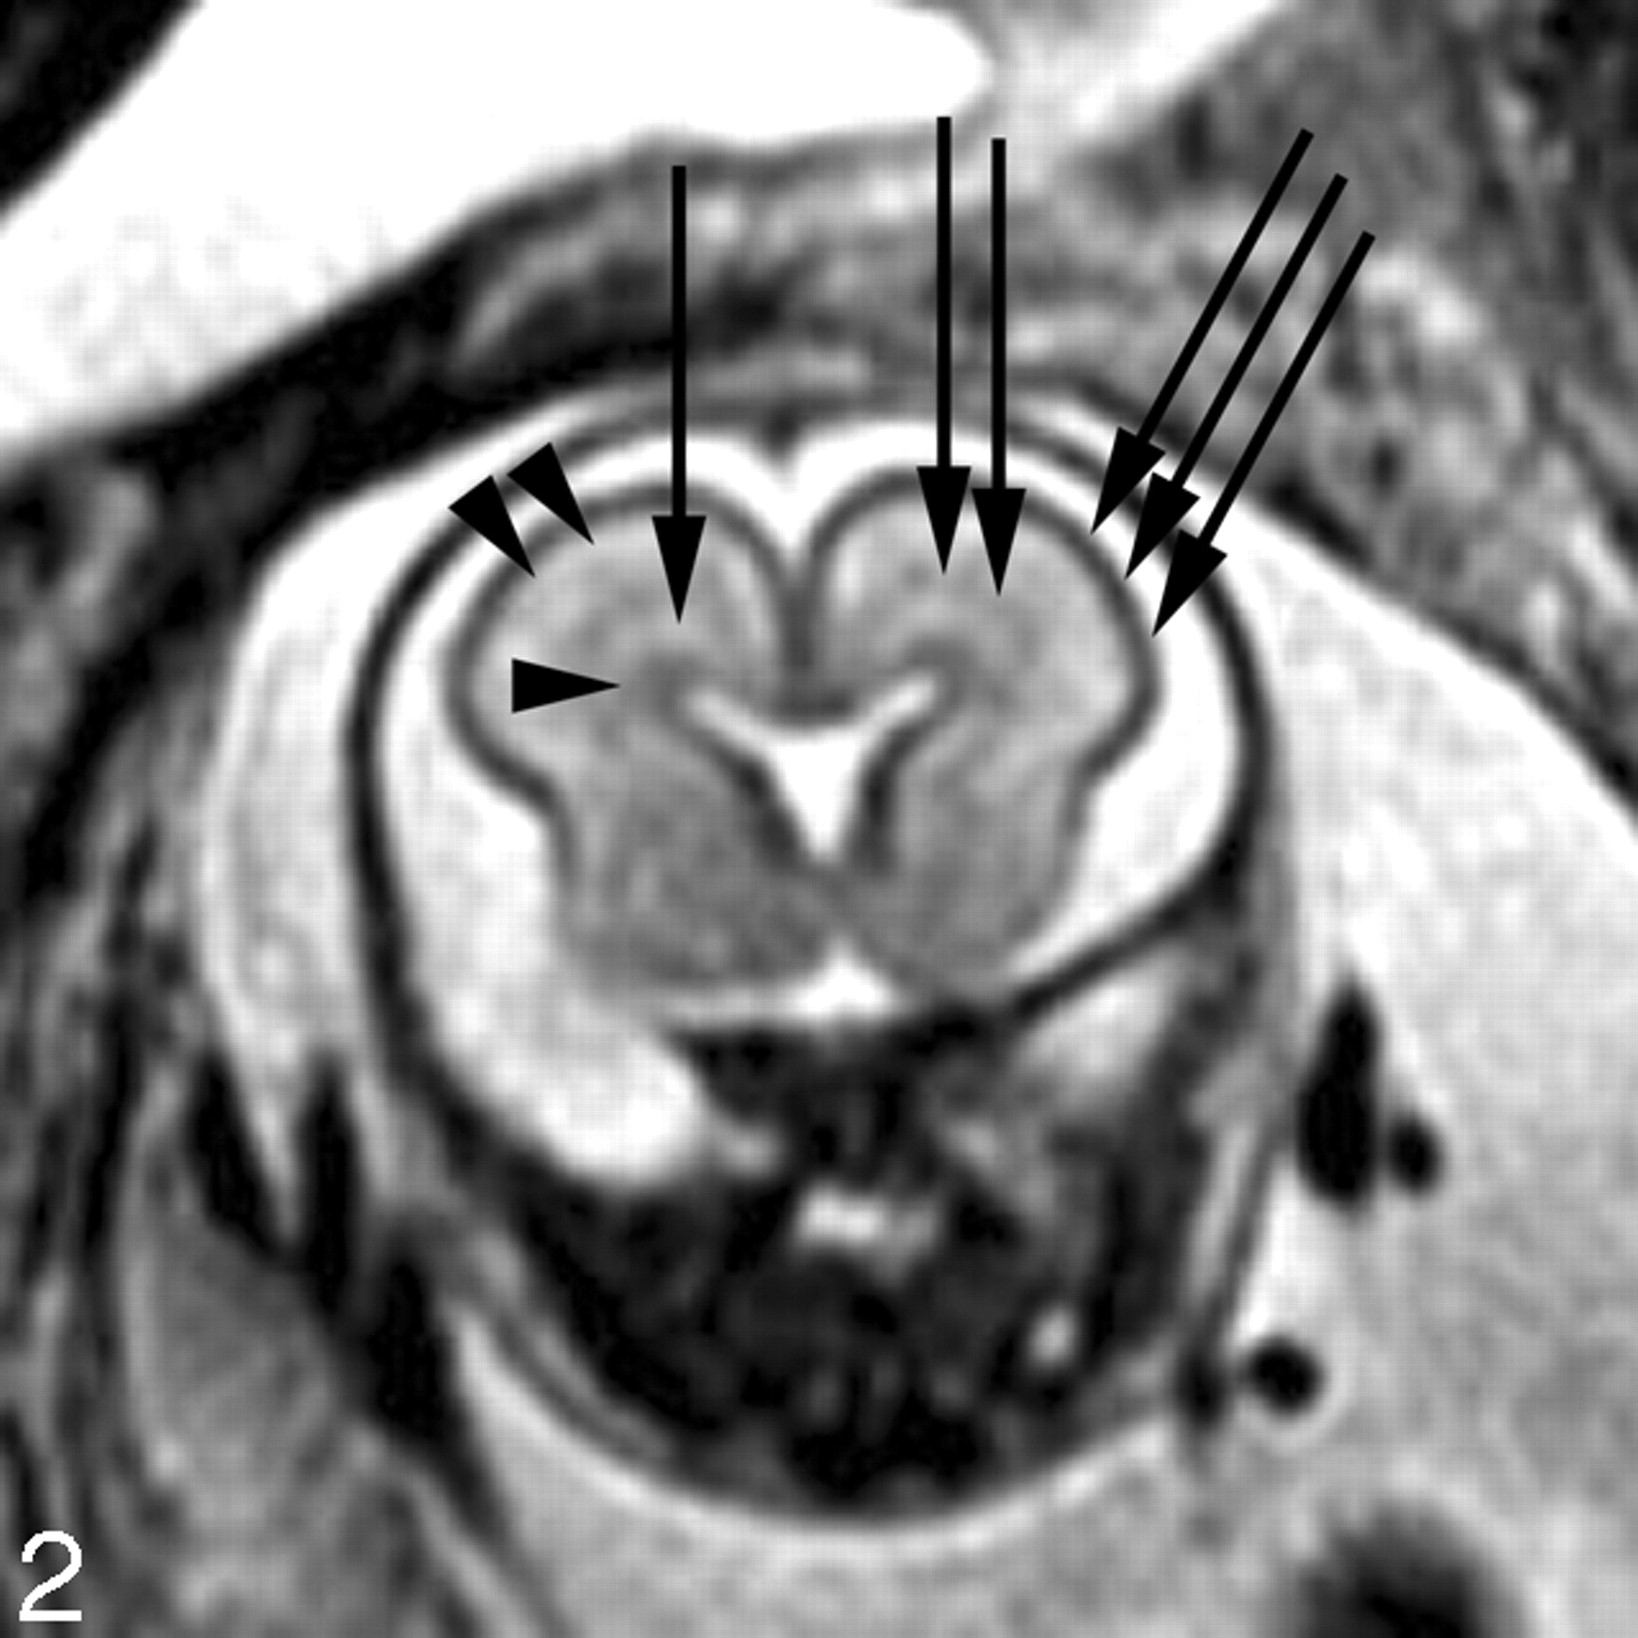

In our experience, fetal MR imaging is especially useful in detecting malformations of cortical development in fetuses with sonographically isolated ventriculomegaly. When interpreting fetal MR images in this clinical setting, the margins of the lateral ventricles should be carefully scrutinized for any areas of nodularity that may represent periventricular nodular heterotopia. Such nodules are isointense to the germinal matrix (Fig 4). Periventricular nodular heterotopia, however, are indistinguishable from the subependymal nodules present in tuberous sclerosis, and other manifestations of tuberous sclerosis, such as transmantle dysplasias, cortical tubers, and cardiac rhabdomyoma, should be sought when ventricular nodularity is identified (Fig 5). Cortical malformations, such as polymicrogyria, can be identified by noting alteration of the normal sulcation pattern for a fetus’ particular gestational age (Fig 6A); they may be identified as too many sulci in a less mature fetus or as too few or abnormally deep or abnormally located sulci in a more mature fetus. The identification of malformations of cortical development in the setting of ventriculomegaly should raise the possibility of a genetic (including metabolic disturbances) or an infectious cause of the ventriculomegaly.

A, 22-week old fetus with several nodular areas of low signal intensity along the margin of the left lateral ventricle (arrows) on axial SS-FSE T2-weighted image. This was confirmed on coronal SS-FSE T2-weighted images (not shown) and is consistent with periventricular nodular heterotopia; and was confirmed at autopsy.

B, 23-week-old fetus with smaller nodular area of low signal intensity along the atrium of the right lateral ventricle (arrow) on coronal SS-FSE T2-weighted image. Finding was confirmed on axial image (not shown). Findings are also consistent with periventricular nodular heterotopia in this fetus with a family history of periventricular nodular heterotopia.